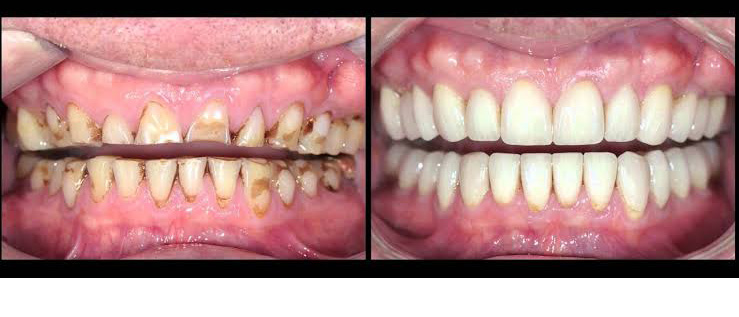

Full mouth reconstruction (or full mouth rehabilitation) refers to restoration or replacement of all or most of the damaged and missing teeth in a patient’s mouth. It is basically an inter disciplinary treatment required to rejuvenate oral health and overall wellbeing. Patients can get a new life with full moth reconstruction.

• Chipped, cracked or worn out teeth

• Injured or fractured teeth